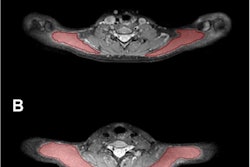

RSNA is still targeted by many groups of researchers from international centers of excellence. For example, presenters from University Hospital Ulm and University Hospital Rechts der Isar in Germany unveiled MRI results suggesting that increased T2 values of the trapezius muscles could be an objective imaging biomarker for myofascial involvement in primary headache disorders.